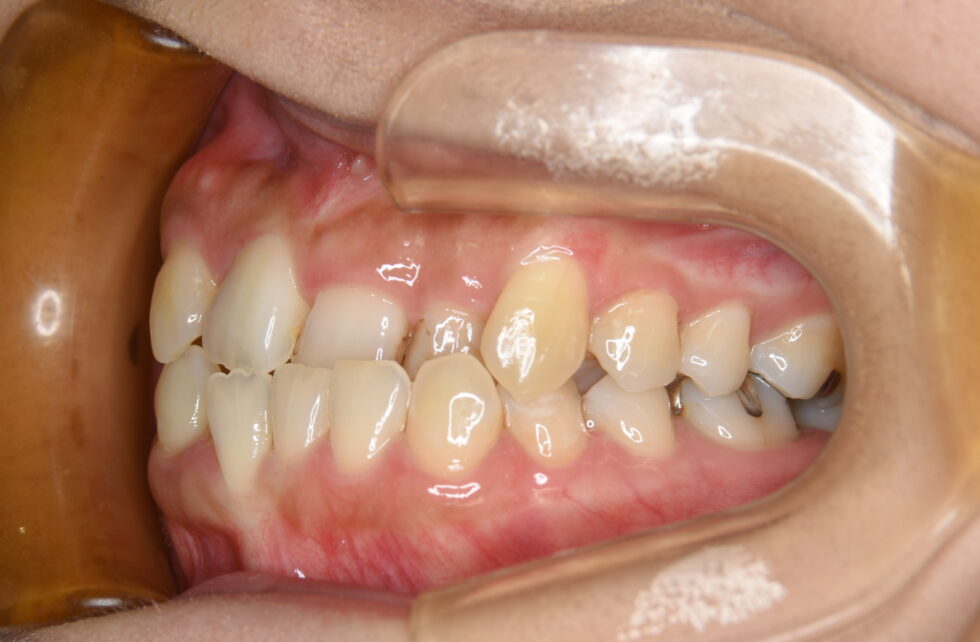

初診時年齢32歳の女性 前歯部の叢生と反対咬合を主訴にご来院いただいた

上顎は右側側切歯が口蓋側転位となり、その分上顎の正中線は右側へ4㎜程度偏位していた。また、右側第二小臼歯は残根状態で歯冠が無かった。さらに、左側中切歯、側切歯は反対咬合となっていた。上顎右側に矯正用アンカープレートを植立し、上顎は左右側第二小臼歯、下顎は左右側第一小臼歯を抜歯していただきマルチブラケット装置を使用して動的治療を行った。上顎右側側切歯が完全に口蓋側転位になっているにもかかわらず、残根となっていた第二小臼歯を抜歯する必要があったため、上顎右側第一小臼歯と犬歯の遠心への移動に時間がかかり動的治療期間は3年5ヵ月間を要した。(調整来院30回)しかし、可能な限り健全な歯を残すことができた。また、虫歯のリスクが高い方であったが歯列が整ったことでセルフケアがしやすくなった。